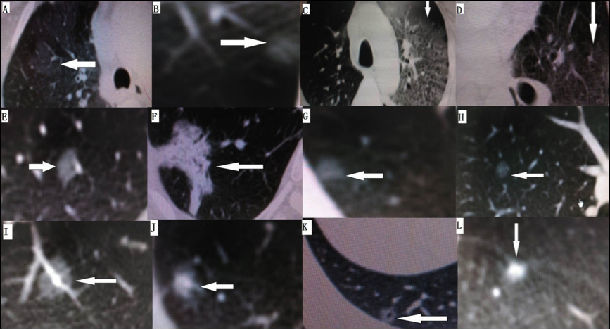

人类你好,我有一个很有趣的名字,中文叫肺部磨玻璃影,英文叫GGO。你们在胸部计算机断层扫描 (Computer Tomography,CT )检查时发现了我,表现为密度轻度增高的云雾状淡薄影,样子与磨砂玻璃一样,所以叫我GGO。我可以弥漫性散在生长(图A),也可以仅聚集在局部,看起来像一个小磨玻璃结节(图B)。

大家不要谈我色变哦,我不一定是坏人(cancer,ca, 癌)。有时候,肺部炎症(图C)、 出血(图D) 、 纤 维 化(炎症后遗留的瘢痕)(图E )都可以造就我,然而,我在更多的时候还是坏人,江湖险恶,好人太少哦。我从小就有个理想:我要争夺身体的控制权,我要当老大!

我肯定是从小逐渐长到大的哦,不会一开始就变成巨无霸(图f)。我小时候(<1厘米)很纯、密度很低、圆脸、边界也清晰,这时我还不一定是坏人,你们叫我纯 GGO(图B),切除后多证实为腺瘤样不典型增生(AAH,癌前病变) (图G), 或者是原位腺癌(TIS,对周围血管间质没有侵犯,不会转移)(图H),甚至极端情况下也可能是微浸润腺癌(MIS,对周围血管间质侵犯<5毫米,潜在转移风险)(图I)。

当我逐渐长大变坏时,可能会引起实性成分增加,变得不那么纯了,你们叫我混合性GGO(图J);有时,我还会出现分叶、毛刺(图F)、空泡(图K),胸膜凹陷(图L),血管密集等改变,这时我多数已经是坏人了,你们叫我浸润性腺癌、恶性肿瘤。我体内的细胞子民喜欢进入人类的血管,遨游在红色的海洋里,任意选址安营扎寨,你们把这叫做转移,但只有这样,我这个老大当得才叫名符其实,手下有人,不是么?